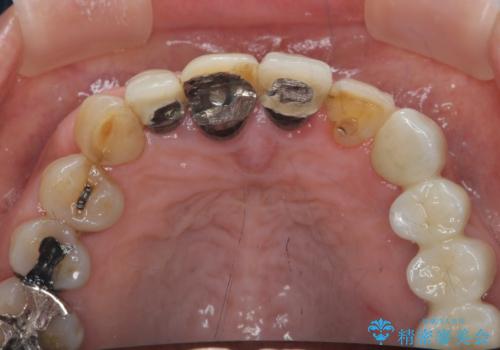

1. ぐらつく前歯 ブリッジ治療の治療前